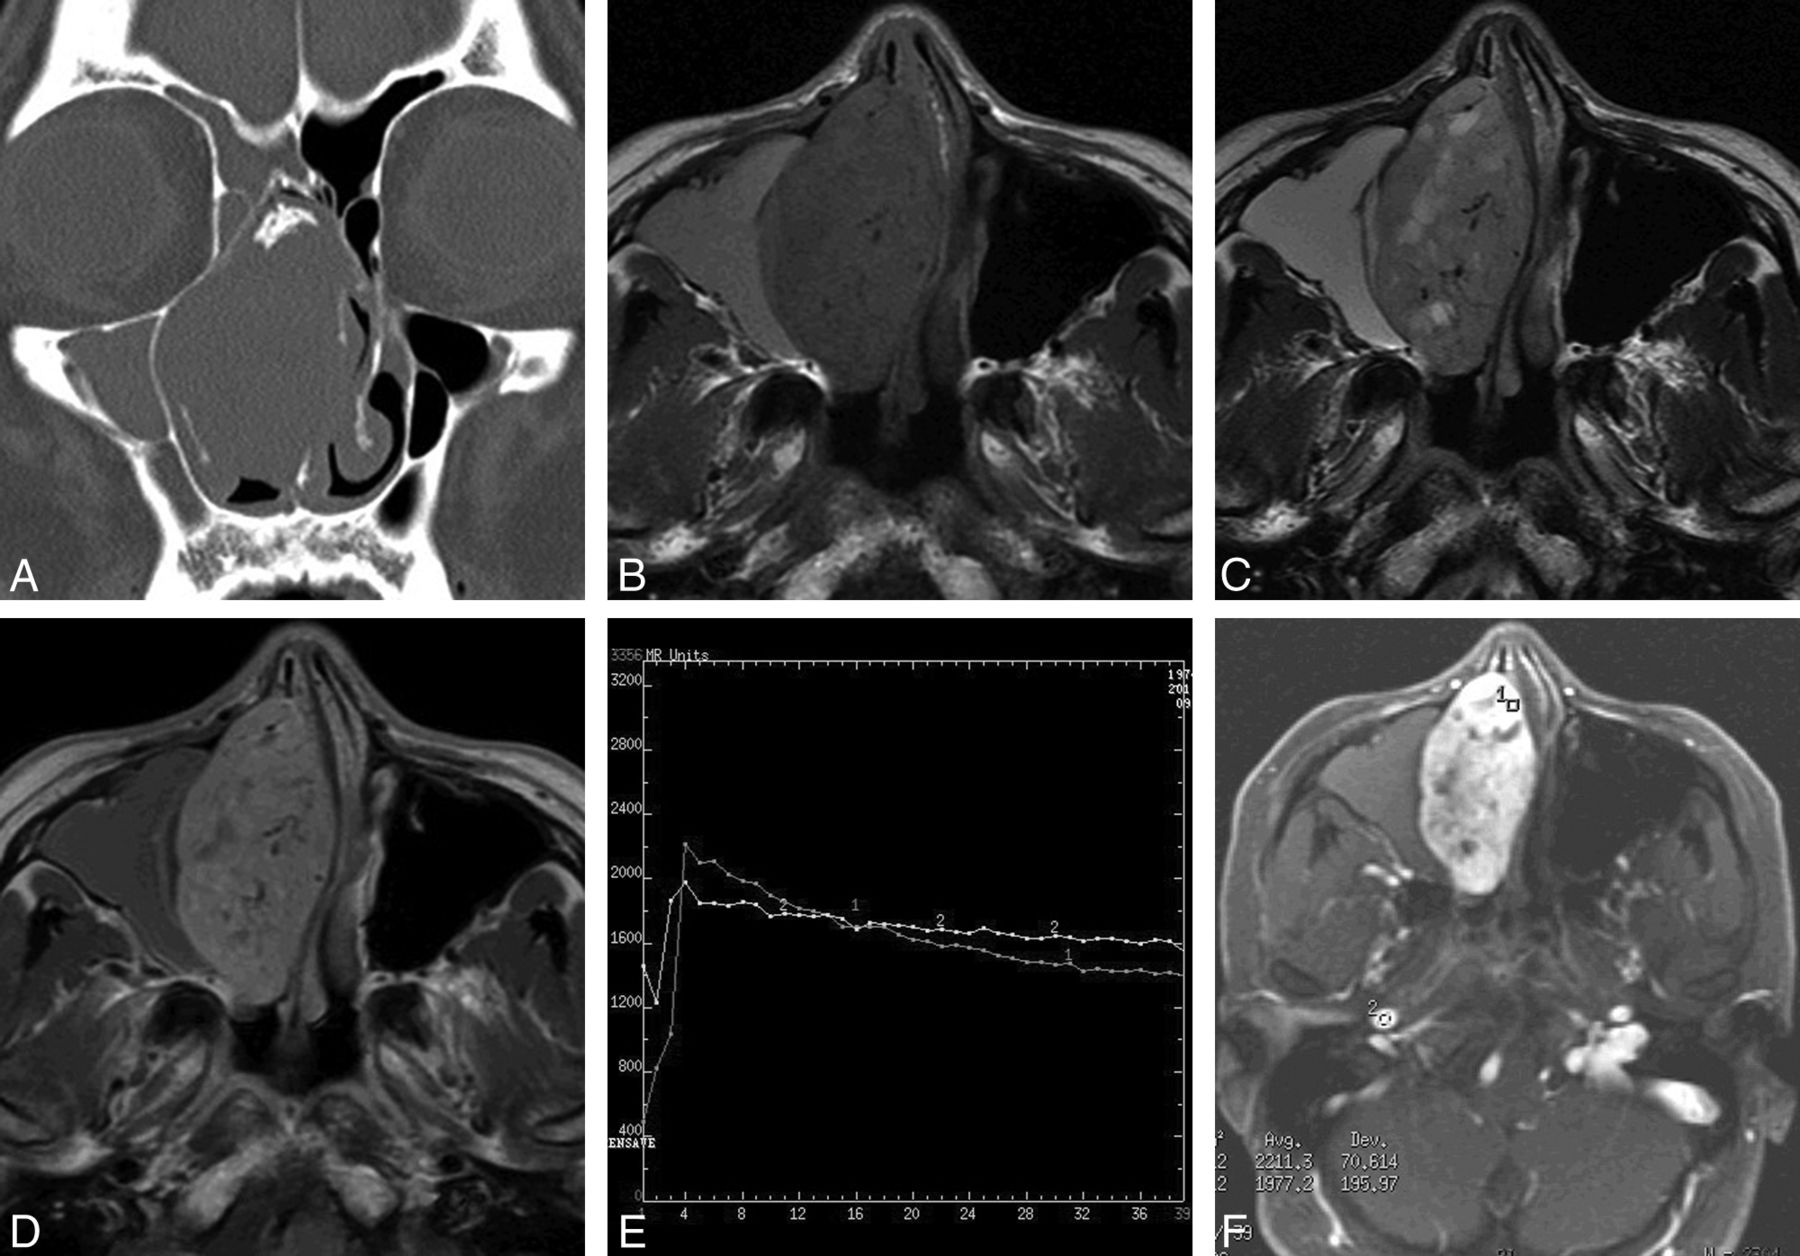

Case 2. A, Coronal CT scan with a bone algorithm shows an oblong well-defined mass in the right nasal cavity with patchy calcification. Note remodeling, thinning, and local absorption of the adjacent bony walls. B, Axial T1-weighted MR image shows a homogeneous isointense signal mass with multiple flow voids in the right nasal cavity. Note the lesion of high signal intensity in the right maxillary sinus. C, Axial T2-weighted MR image shows a heterogeneous isointense signal mass with multiple patchy high-signal-intensity areas, which have no enhancement on the corresponding contrast-enhanced MR images, suggesting cystic degeneration. The lesion in the right maxillary sinus also demonstrates high signal intensity. D, Axial contrast-enhanced MR image shows heterogeneously marked tumor enhancement with multiple flow voids. No enhancement of the lesion of the right maxillary sinus is noted, indicating obstructive maxillary sinusitis. E, Corresponding axial dynamic contrast-enhanced MR image depicts a washout pattern (type III) TIC. F, The round cursors mark the ROIs of the lesion and the right internal carotid artery selected for signal-intensity measurement at dynamic MR imaging.

Five SFTs appeared homogeneously isointense on T1-weighted images relative to gray matter (Figs 1B and 2A). On T2-weighted images, these lesions showed heterogeneous hypointensity in 2 and isointensity in 3 patients (Figs 1C and 2B). The lesions typically demonstrated heterogeneously marked enhancement on the enhanced MR images (Figs 1D and 2C). Multiple tubular flow voids were demonstrated in 2 patients (Fig 1B–D). One patient also had intratumoral cystic areas, which showed hypointensity on the T1-weighted imaging and hyperintensity on the T2-weighted imaging, without contrast enhancement (Fig 1B–D). Two patients had associated obstructive maxillary sinusitis, and 1 patient had obstructive sphenoid sinusitis, which produced high signal on both the T1- and T2-weighted images, without contrast enhancement (Fig 1B–D). One patient's tumor extended into the adjacent nasal cavity and infratemporal and pterygopalatine fossae. Four patients underwent dynamic contrast-enhanced MR imaging, and the TICs revealed a washout pattern (type III), which was similar to that of the internal carotid artery (Fig 1E, -F).

Case 4. A, Axial T1-weighted MR image shows an oblong well-defined homogeneous isointense signal mass in the left nasal cavity. B, Axial T2-weighted MR image shows a mass with heterogeneous hypointense signal. C, Axial contrast-enhanced MR image with fat saturation shows heterogeneous marked tumor enhancement.